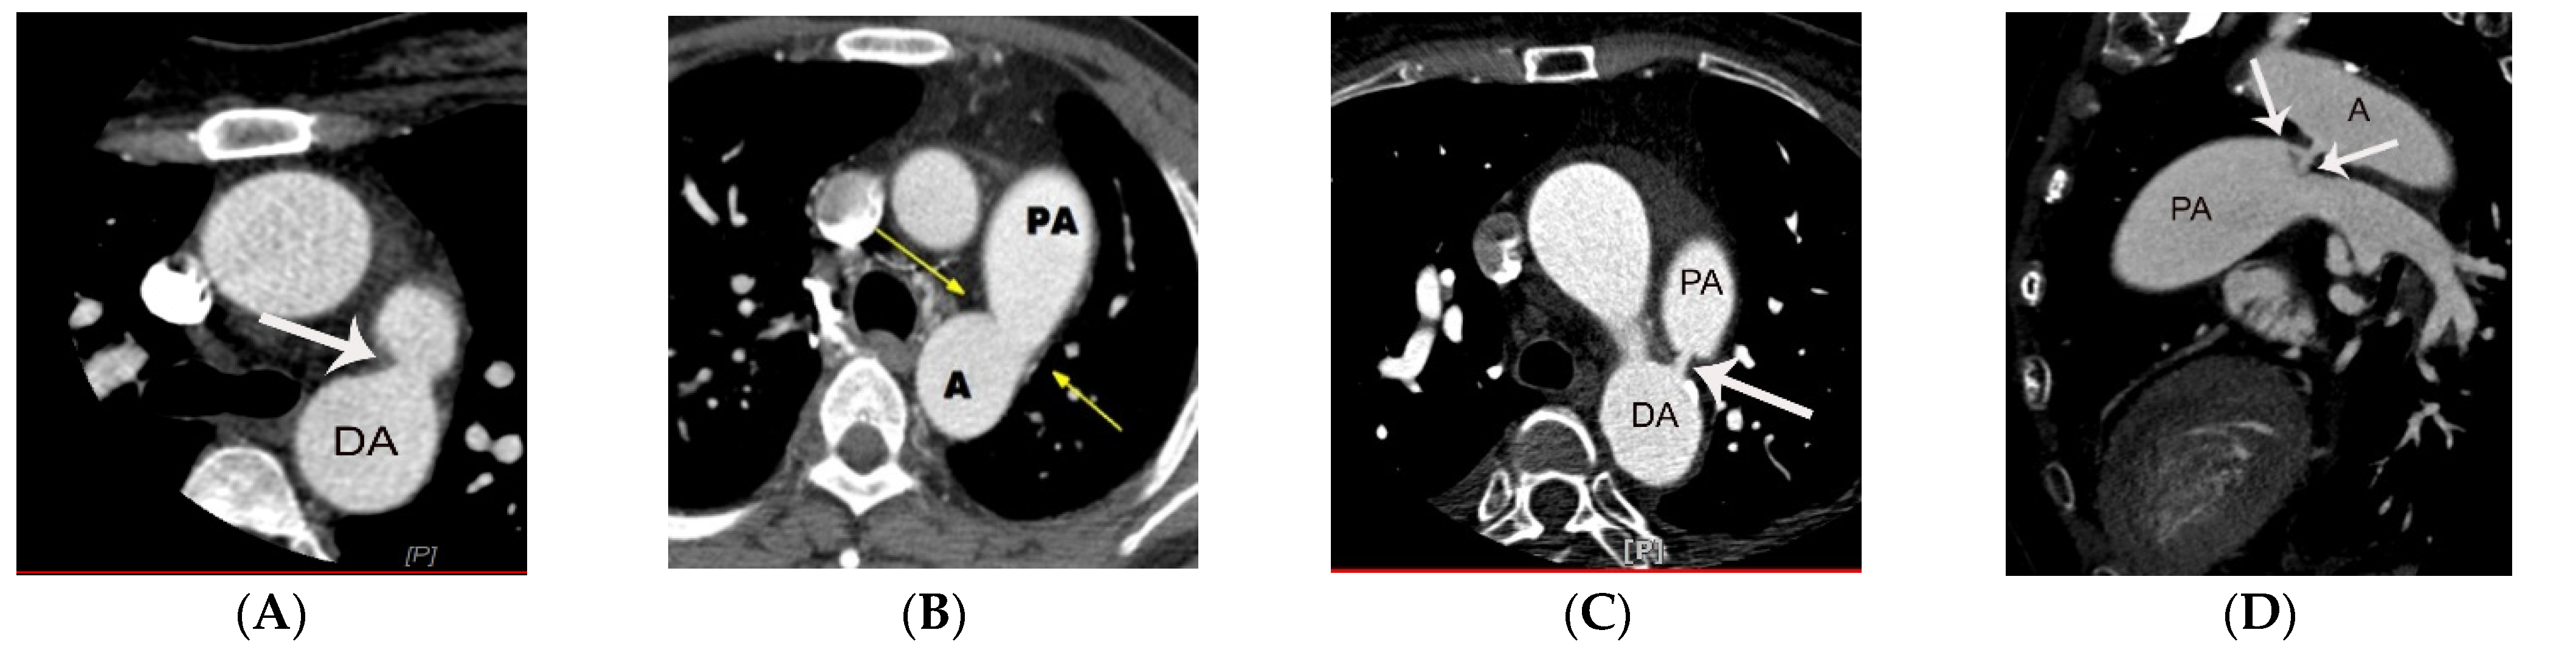

5. CT Anatomy of PDA

6.1. Potential Role of CT in Moderate-to Large-Sized PDA

6.2. Potential Role of CT in Small PDAs